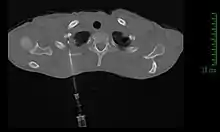

La méthode de diagnostic la plus précise est la ponction percutanée trans-thoracique par ponction à l’aiguille, sous contrôle scanner, qui présente un rendement de 95 %[11],[21]. En cas d'échec, il est possible de réaliser une biopsie chirurgicale par thoracoscopie ou thoracotomie[11].